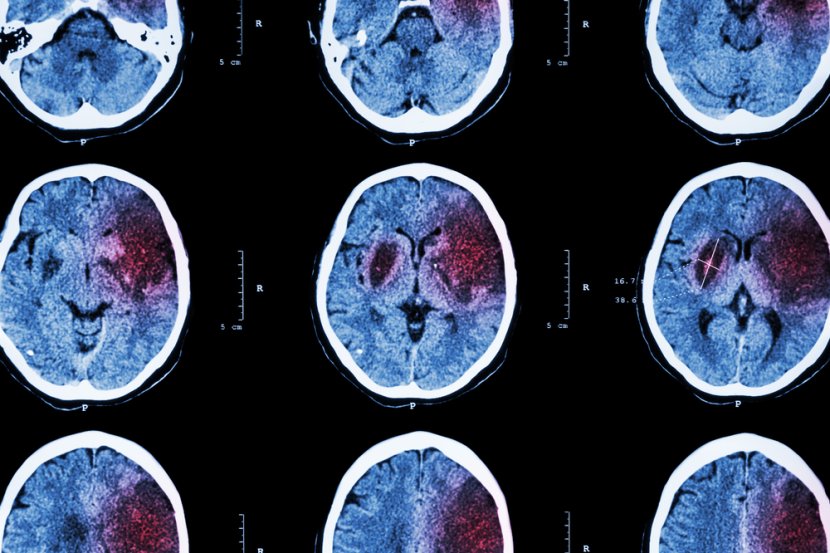

Moždane komplikacije koje izaziva covid 19, odnosno čitav spektar tih poremećaja, proučavala je najveća multiinstitucionalna međunarodna studija do sada i otkrila da će otprilike jedan od 100 pacijenata hospitalizovanih sa covid 19 infekcijom verovatno razviti komplikacije na centralnom nervnom sistemu. To može da uključuje moždani udar, krvarenje i druge potencijalno fatalne komplikacije, a studija sa ovim otrkićima predstavljena je na godišnjem sastanku Radiološkog društva Severne Amerike (RSNA).

Da bi dobili potpuniju sliku, dr Scott H. Faro i njegove kolege analizirali su skoro 40.000 slučajeva hospitalizovanih pacijenata pozitivnih na covid 19 iz sedam američkih i četiri zapadnoevropske univerzitetske bolnice. Pacijenti su primljeni u periodu od septembra 2019. do juna 2020. Njihova prosečna starost bila je 66 godina, a muškaraca je bilo duplo više nego žena.

Najčešći uzrok prijema bila je konfuzija i izmenjen mentalni status, praćen povišenom temperaturom. Mnogi pacijenti su imali komorbiditete kao što su hipertenzija, srčana oboljenja i dijabetesBilo je 442 akutna neuroimidžing nalaza koji su najverovatnije povezani sa virusnom infekcijom. Ukupna incidencija komplikacija na centralnom nervnom sistemu u ovoj velikoj grupi pacijenata iznosila je 1,2 odsto.

- Od svih pacijenata koji su imali snimke kao što su magnetna rezonanca ili CT mozga, pregled je bio pozitivan otprilike 10 odsto vremena. Učestalost od 1,2 procenata znači da će nešto više od jednog od 100 pacijenata primljenih u bolnicu sa covid 19 imati neku vrstu problema sa mozgom - naglasio je dr Faro. Kako je naveo, najčešća komplikacija bio je ishemijski moždani udar, sa incidencom od 6,2 odsto, zatim intrakranijalno krvarenje (3,72 procenata) i encefalitis (0,47 odsto), upala mozga.

Istraživači su takođe otkrili mali procenat neobičnih nalaza, kao što su akutni diseminirajući encefalomijelitis, upala mozga i kičmene moždine i sindrom zadnje reverzibilne encefalopatije, sindrom koji oponaša mnoge simptome moždanog udara.